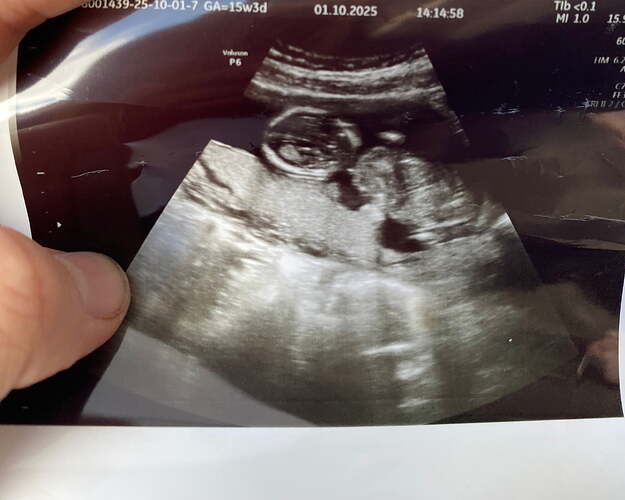

Sizce ney ![]()

![]()

Kese sekli gozukmuyor ki yakından kafa gozukuyor sadece. Uzaktan var mi

Ben şansımı baya zorlamaya çalışıyorum. Sanırım tam cinsiyet öğrenene kadar her gitmemde sana foto ayıcam gibi ![]()